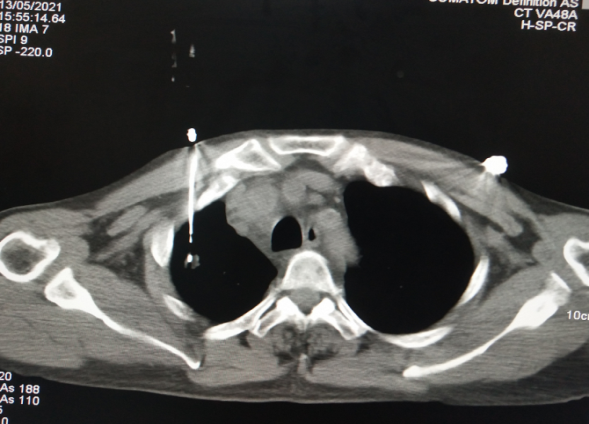

术前病灶测量

术中精准穿刺